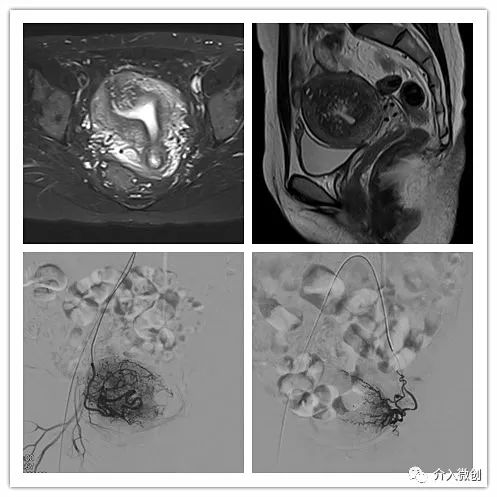

子宫腺肌瘤

中年患者,患有“子宫腺肌瘤”7年余,长期受痛经、月经量增多困扰,严重影响生活质量。经多处求医,经历药物调理、“曼月乐”宫腔植入、“海扶刀”消融术等多种治疗,痛经、月经量多等情况一直无法有效缓解,日渐严重。经UAE治疗后,术后痛经、月经量增多等症状迅速得到缓解,生活质量明显改善。术后3月上述症状基本消失。

- 术前子宫MRI提示宫腔明显增大,诊断为“子宫腺肌瘤”。

- 术后4个月复查,子宫明显缩小,腺肌瘤明显坏死吸收,相关症状基本消失。